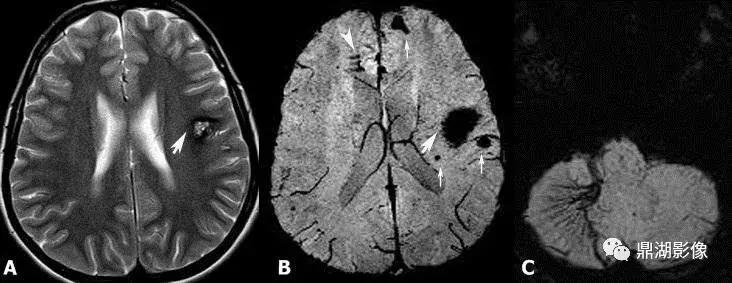

3.MRI表现:T1W呈稍低信号或低信号,有出血时可见不均匀高信号;T2WI可呈高信号,周边可见特征性环状低信号,为含铁血黄素沉着所致。一般不需要强化扫描。MR是最佳的影像检查方法。

补充:其中富含血液的血窦T1WI上呈明显的低信号,T2WI为高信号。病灶中心出血后,含铁血黄素沉积及瘤体钙化及增生的胶质使病灶的T2WI呈混杂信号,病灶周边纤维变性的脑组织形成的假包膜T2WI则显示为环形低信号。磁敏感加权成像技术是以T2*梯度回波序列为基础,利用不同组织间的磁敏感性差异而产生图像对比增强的MR成像方法,可同时获得 磁距 图像和相位图像。由于磁敏感物质可造成局部磁场不均匀性,引起质子失相位,产生顺磁性,在SWI序列上表现为低信号,所以SWI序列对磁敏感物质极为敏感,脑内海绵状血管瘤在SWI像上表现为明显低信号。